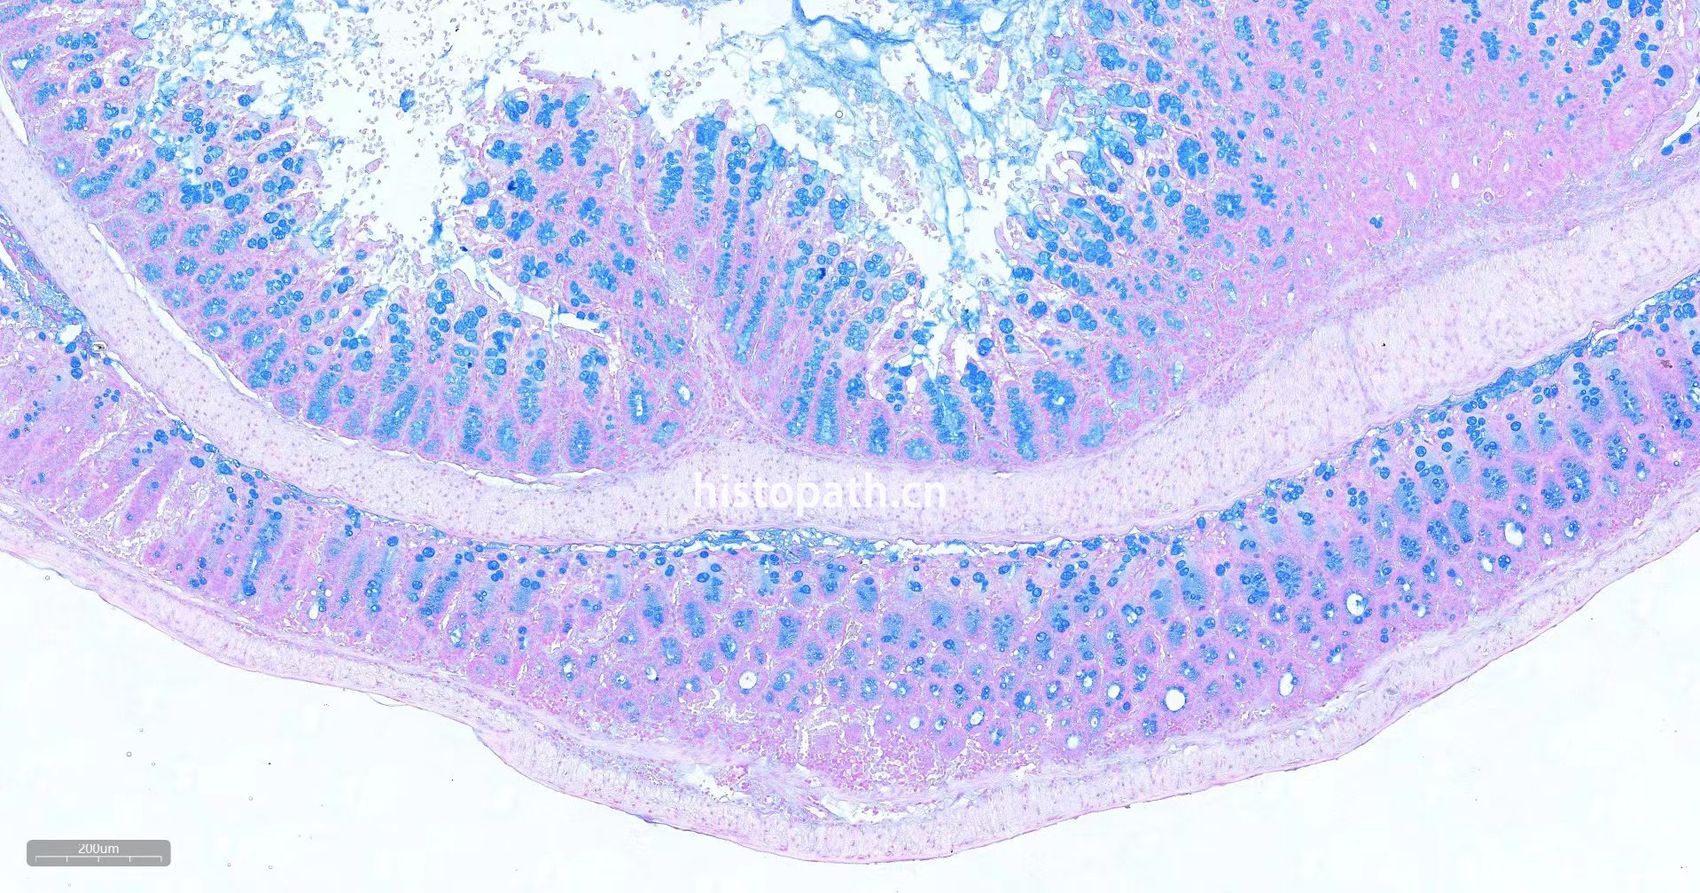

染色结果:

酸性硫酸化粘液物质:蓝色

透明质酸:蓝色

唾液黏蛋白:蓝色

细胞核:红色

瑞士肠卷阿利新蓝染色: